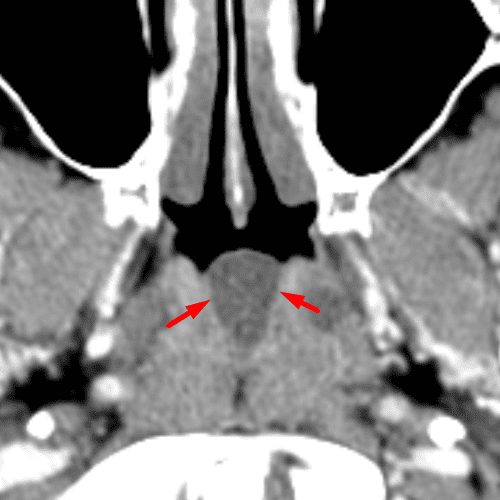

Congenital Anomalies of C1

Case 13

Free